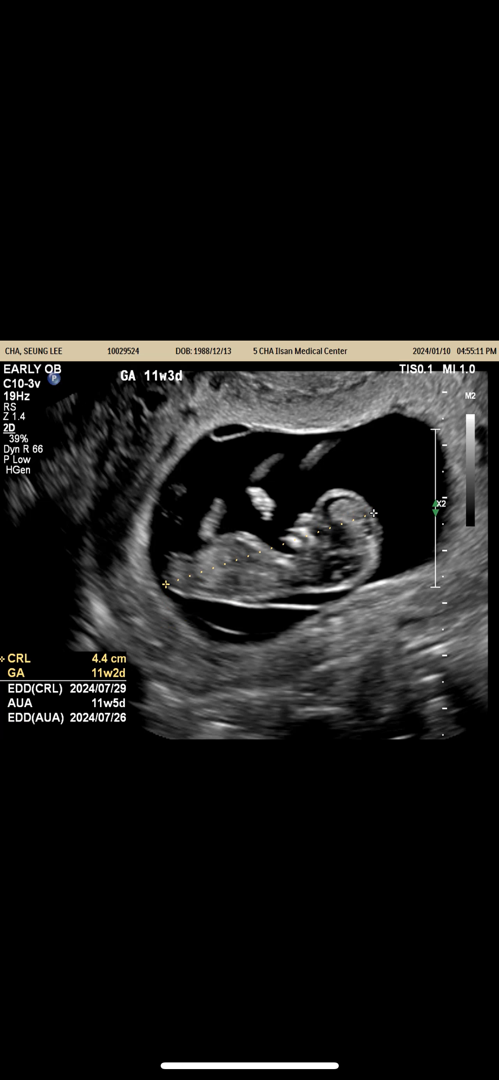

성별 혹시 보이시나요?

사촌언니가 딸같다고 하는데!! 정말 그래보이시나요?ㅠ 궁금해요 너무ㅋㅋㅋ

저각도법 잘보는데. . ㅎㅎ딸입니당

평행해 보여요 저도 딸에 한표요!

각도법 딸 같아요 ㅎㅎ

각도법이 딸같아요 ㅎㅎㅎㅎ